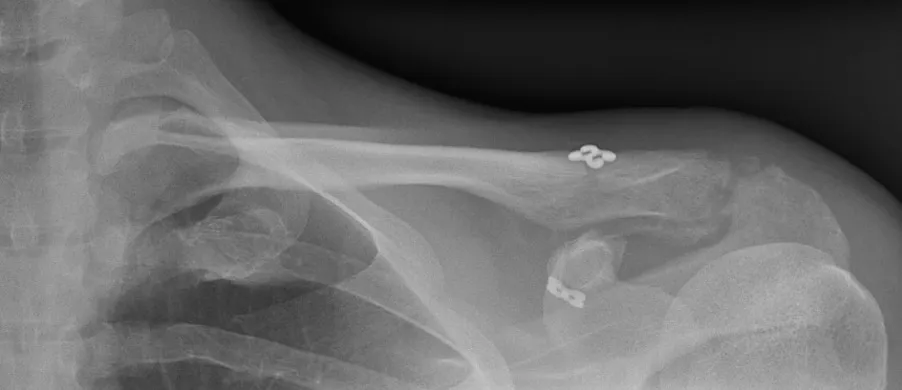

Avant de remonter dans votre chambre vous passerez par la salle de réveil ou une radiographie de contrôle sera réalisée.